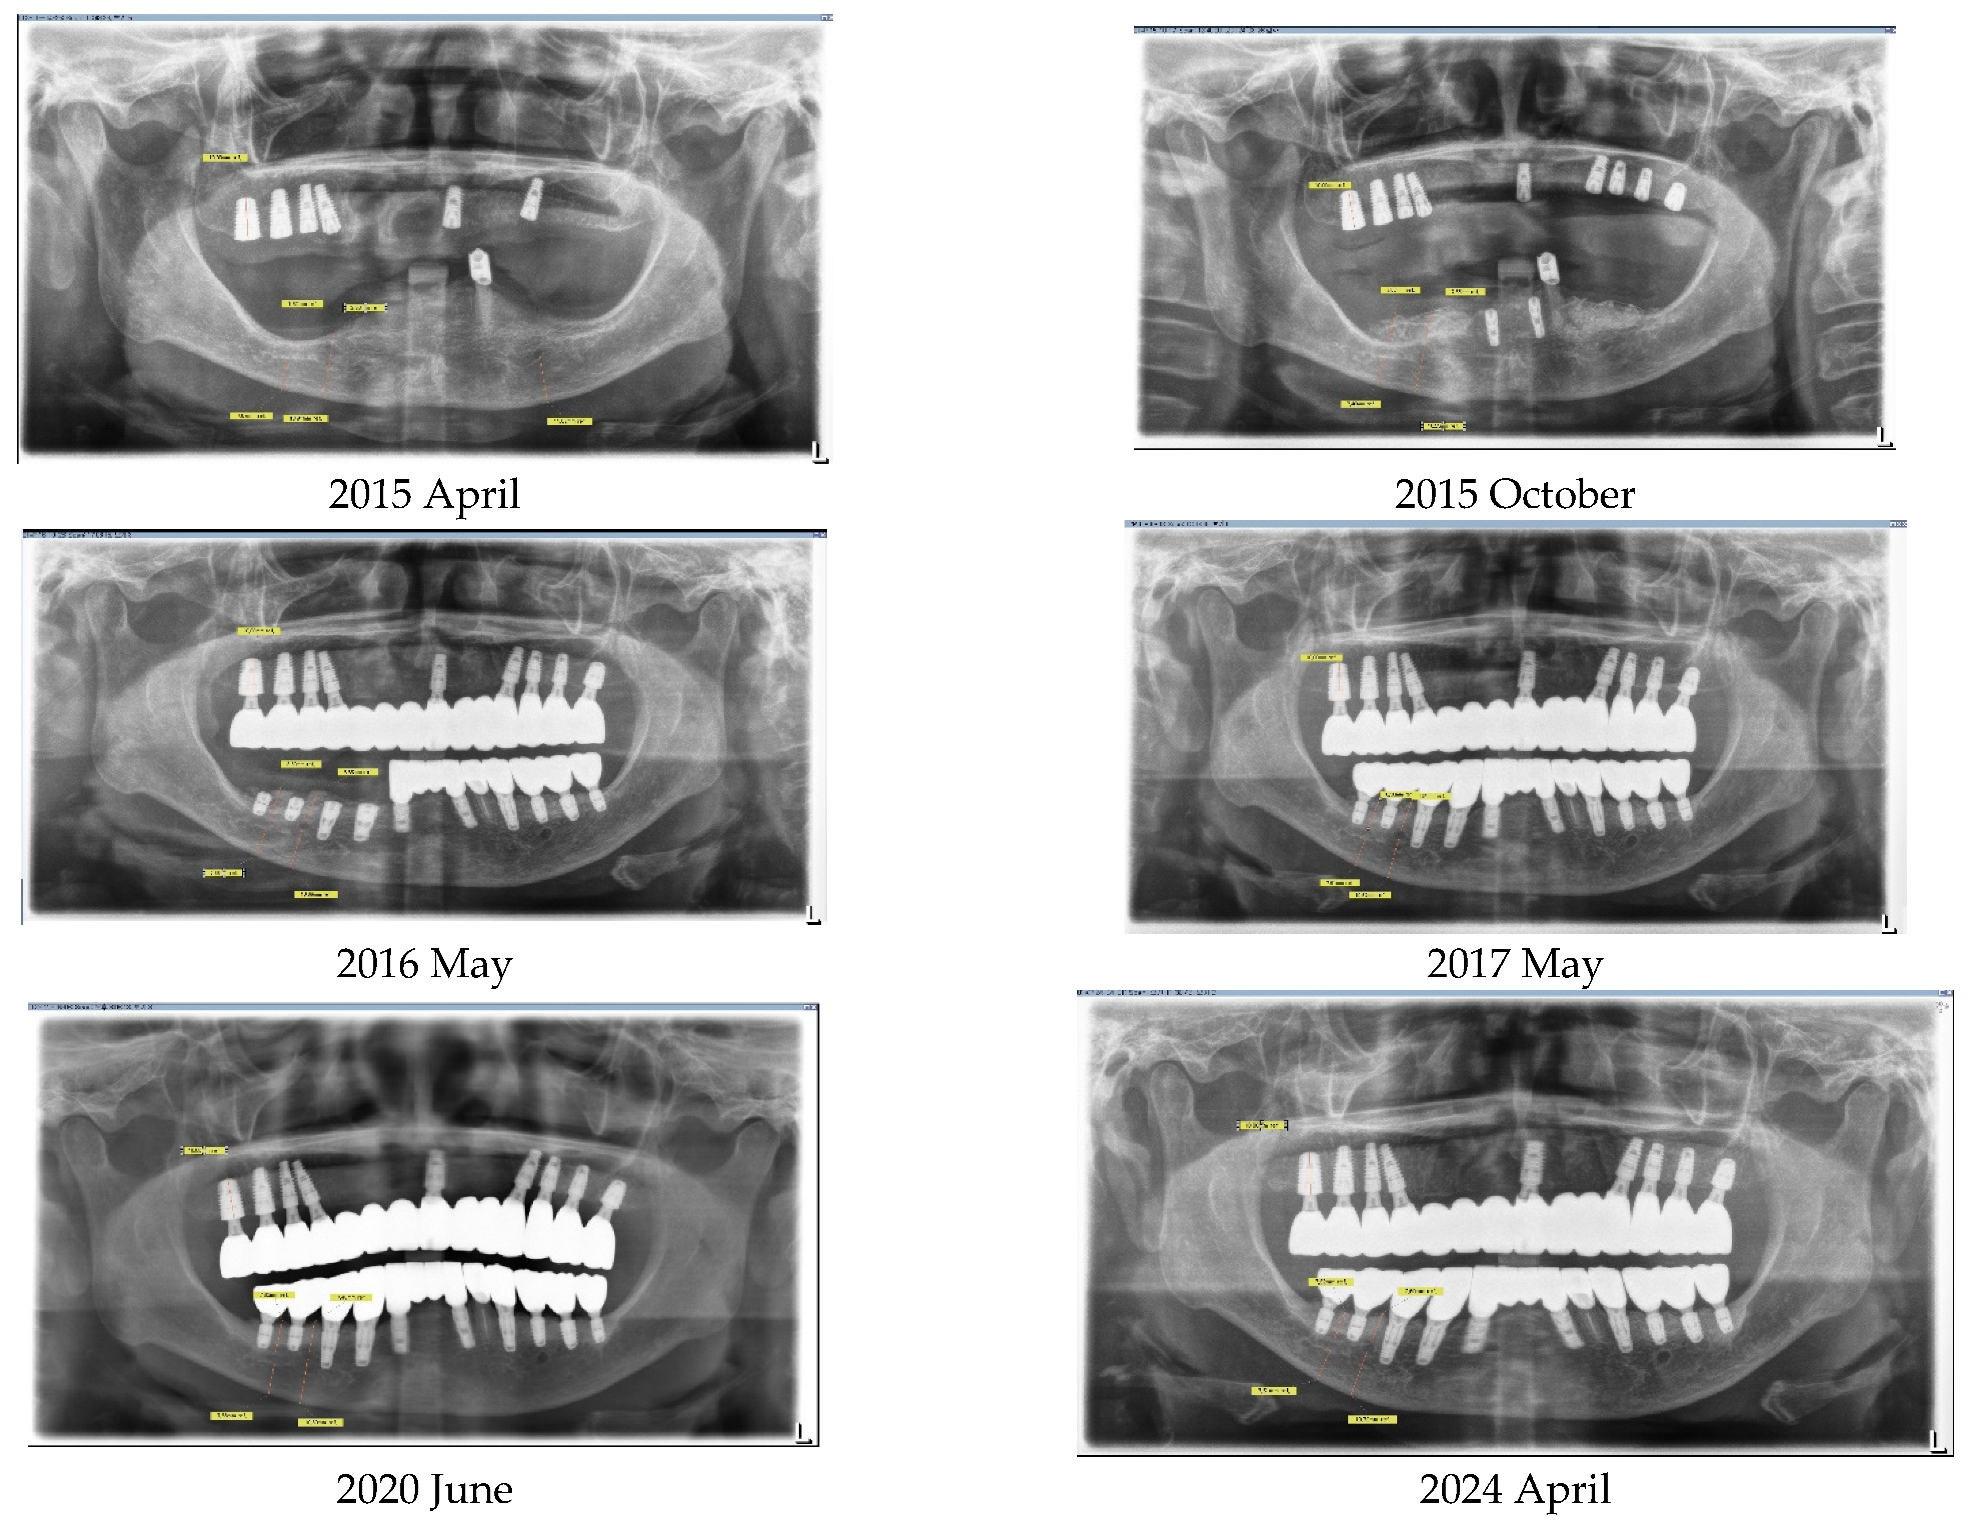

The implant restorations for the lower left posterior area were finalized on 28 September 2016, five months following the implant placements. Subsequently, the restorations for the lower right canine and first premolar were completed on 23 December 2016, seven months post-implantation. The final restorations for the lower right first molar and second molar were accomplished on 2 May 2017, six months after their implantation. This marked the conclusion of all fixed prosthesis work, spanning a total of 23 months from the beginning to the end of the treatment process (Figure 7).

Throughout all procedures, the patient tolerated the treatments well, experiencing no surgical complications such as nerve injury or wound infection. She used temporary removable dentures; however, during the critical postoperative period, which lasted about 2 months, she was advised against wearing them to avoid potential surgical complications from trauma. After this critical period, she was allowed to wear the temporary removable dentures, provided they were adjusted to alleviate pressure on the surgical site. The patient’s chewing ability was effectively restored, with occlusion being verified using Shimstock. The graft bone demonstrated stable results, showing no signs of inflammation or resorption. The implants were functioning well, with no mobility or pain reported. The patient expressed satisfaction with the outcome (Figure 8).

The patient’s masticatory function has been almost fully restored, without any discomfort or difficulties during eating. Her appearance looks natural, as though she had her natural teeth, even though she does not (Figure 9).

Figure 7. On 2 May 2017, the fixed restorations with implants for the lower arch were completed, 23 months after the commencement of the procedure, through vertical bone grafting via SITE. The completion on the right side was delayed compared to the left side due to the need for more bone regeneration, although both sides underwent the same procedure. Please compare the before-and-after treatment pictures.

Figure 9. The lower pictures were taken on 2 May 2023, and 9 January 2024, each six years and seven years after the final finishing, respectively. Please compare them with the initial pictures taken before treatment. The rehabilitation using SITE has shown stable results throughout the follow-up period.